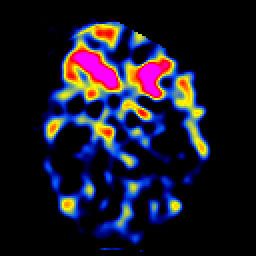

SPECT TL Study #5 -- Slice #21